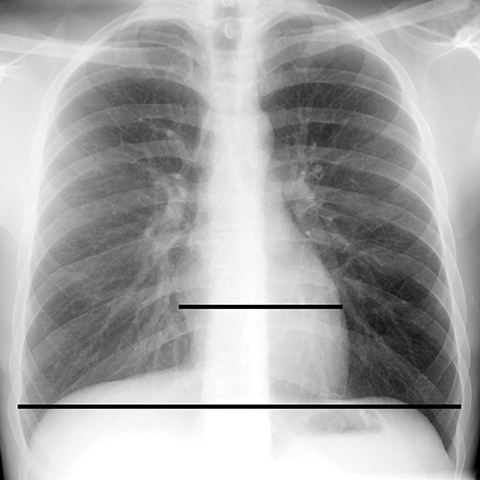

Cardiothoracic Ratio in Normal Heart [1 of 2]

Lines